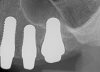

Fig 12. Ceramic implants placed and sutured.

Figure 12

Fig 13. Lateral view after placement.

Figure 13

Figure 10 through Figure 13 show the preoperative x-ray and the sequence of beginning with healed sites through the surgical placement of the implants. The implants were protected by an Essix-style wound-protection removable retainer for approximately 12 weeks. After the integration phase, the implants and the natural dentition were prepared using traditional crown-and-bridge high-speed diamond and zirconia cutting burs to remove decay and existing restorative materials, to complete and refine the natural-tooth structures to receive full-crown coverage, and to prepare and refine gingival margins of the zirconia implants where needed.